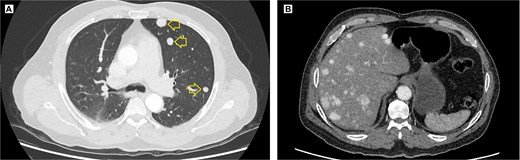

The pelvic radiograph showed a lytic lesion measuring 8 × 8 cm on the outer edge of the right iliac bone (Fig. 1), which was initially considered as a giant cell tumor. Given these findings, a computed tomography (CT) scan of the thorax, abdomen, and pelvis was requested to evaluate possible tumor dissemination. The CT scan revealed a heterogeneous expansive mass measuring 113 × 96 × 100 mm with destruction and remodelation of the right iliac bone (Fig. 2), a 45 × 38 mm mass in the right chest wall with heterogeneous contrast (Fig. 3), three pulmonary nodules in the left lower lobe (5–12 mm) (Fig. 4A) and multiple hypo- and isodense hepatic lesions (10–28 mm in both hepatic lobes) (Fig. 4B). That same month, two biopsies were performed. The first, from the right chest lesion, showed positivity for CD34, BCL-2, and STAT6 in the immunohistochemical study, confirming the presence of an SFT. The second, from the right iliac crest lesion, showed a spindle-cell sarcoma with bone invasion, with immunohistochemistry positive for CD34 and vimentin, a Ki-67 index of 10%, and negative for cytokeratins. This biopsy was processed in a public hospital pathology laboratory, where reagents for BCL-2 and STAT6 were not available at the time of analysis. Based on the histologic appearance, partial immunophenotype, and clinical context, the iliac lesion was considered highly suggestive of metastasis from the chest wall tumor. However, due to the patient’s rapid clinical deterioration and subsequent death, confirmatory testing by STAT6 immunostaining could not be performed.

Contrast-enhanced thoracic and abdominal CT scan. (A) Axial view in the lung window of the thorax, solid hyperenhancing parenchymal nodules (arrow) ranging from 5 to 12 mm are observed in the left lung. (B) Coronal view in the soft tissue window, solid hyperenhancing nodules measuring 10 to 28 mm with diffuse distribution are observed.